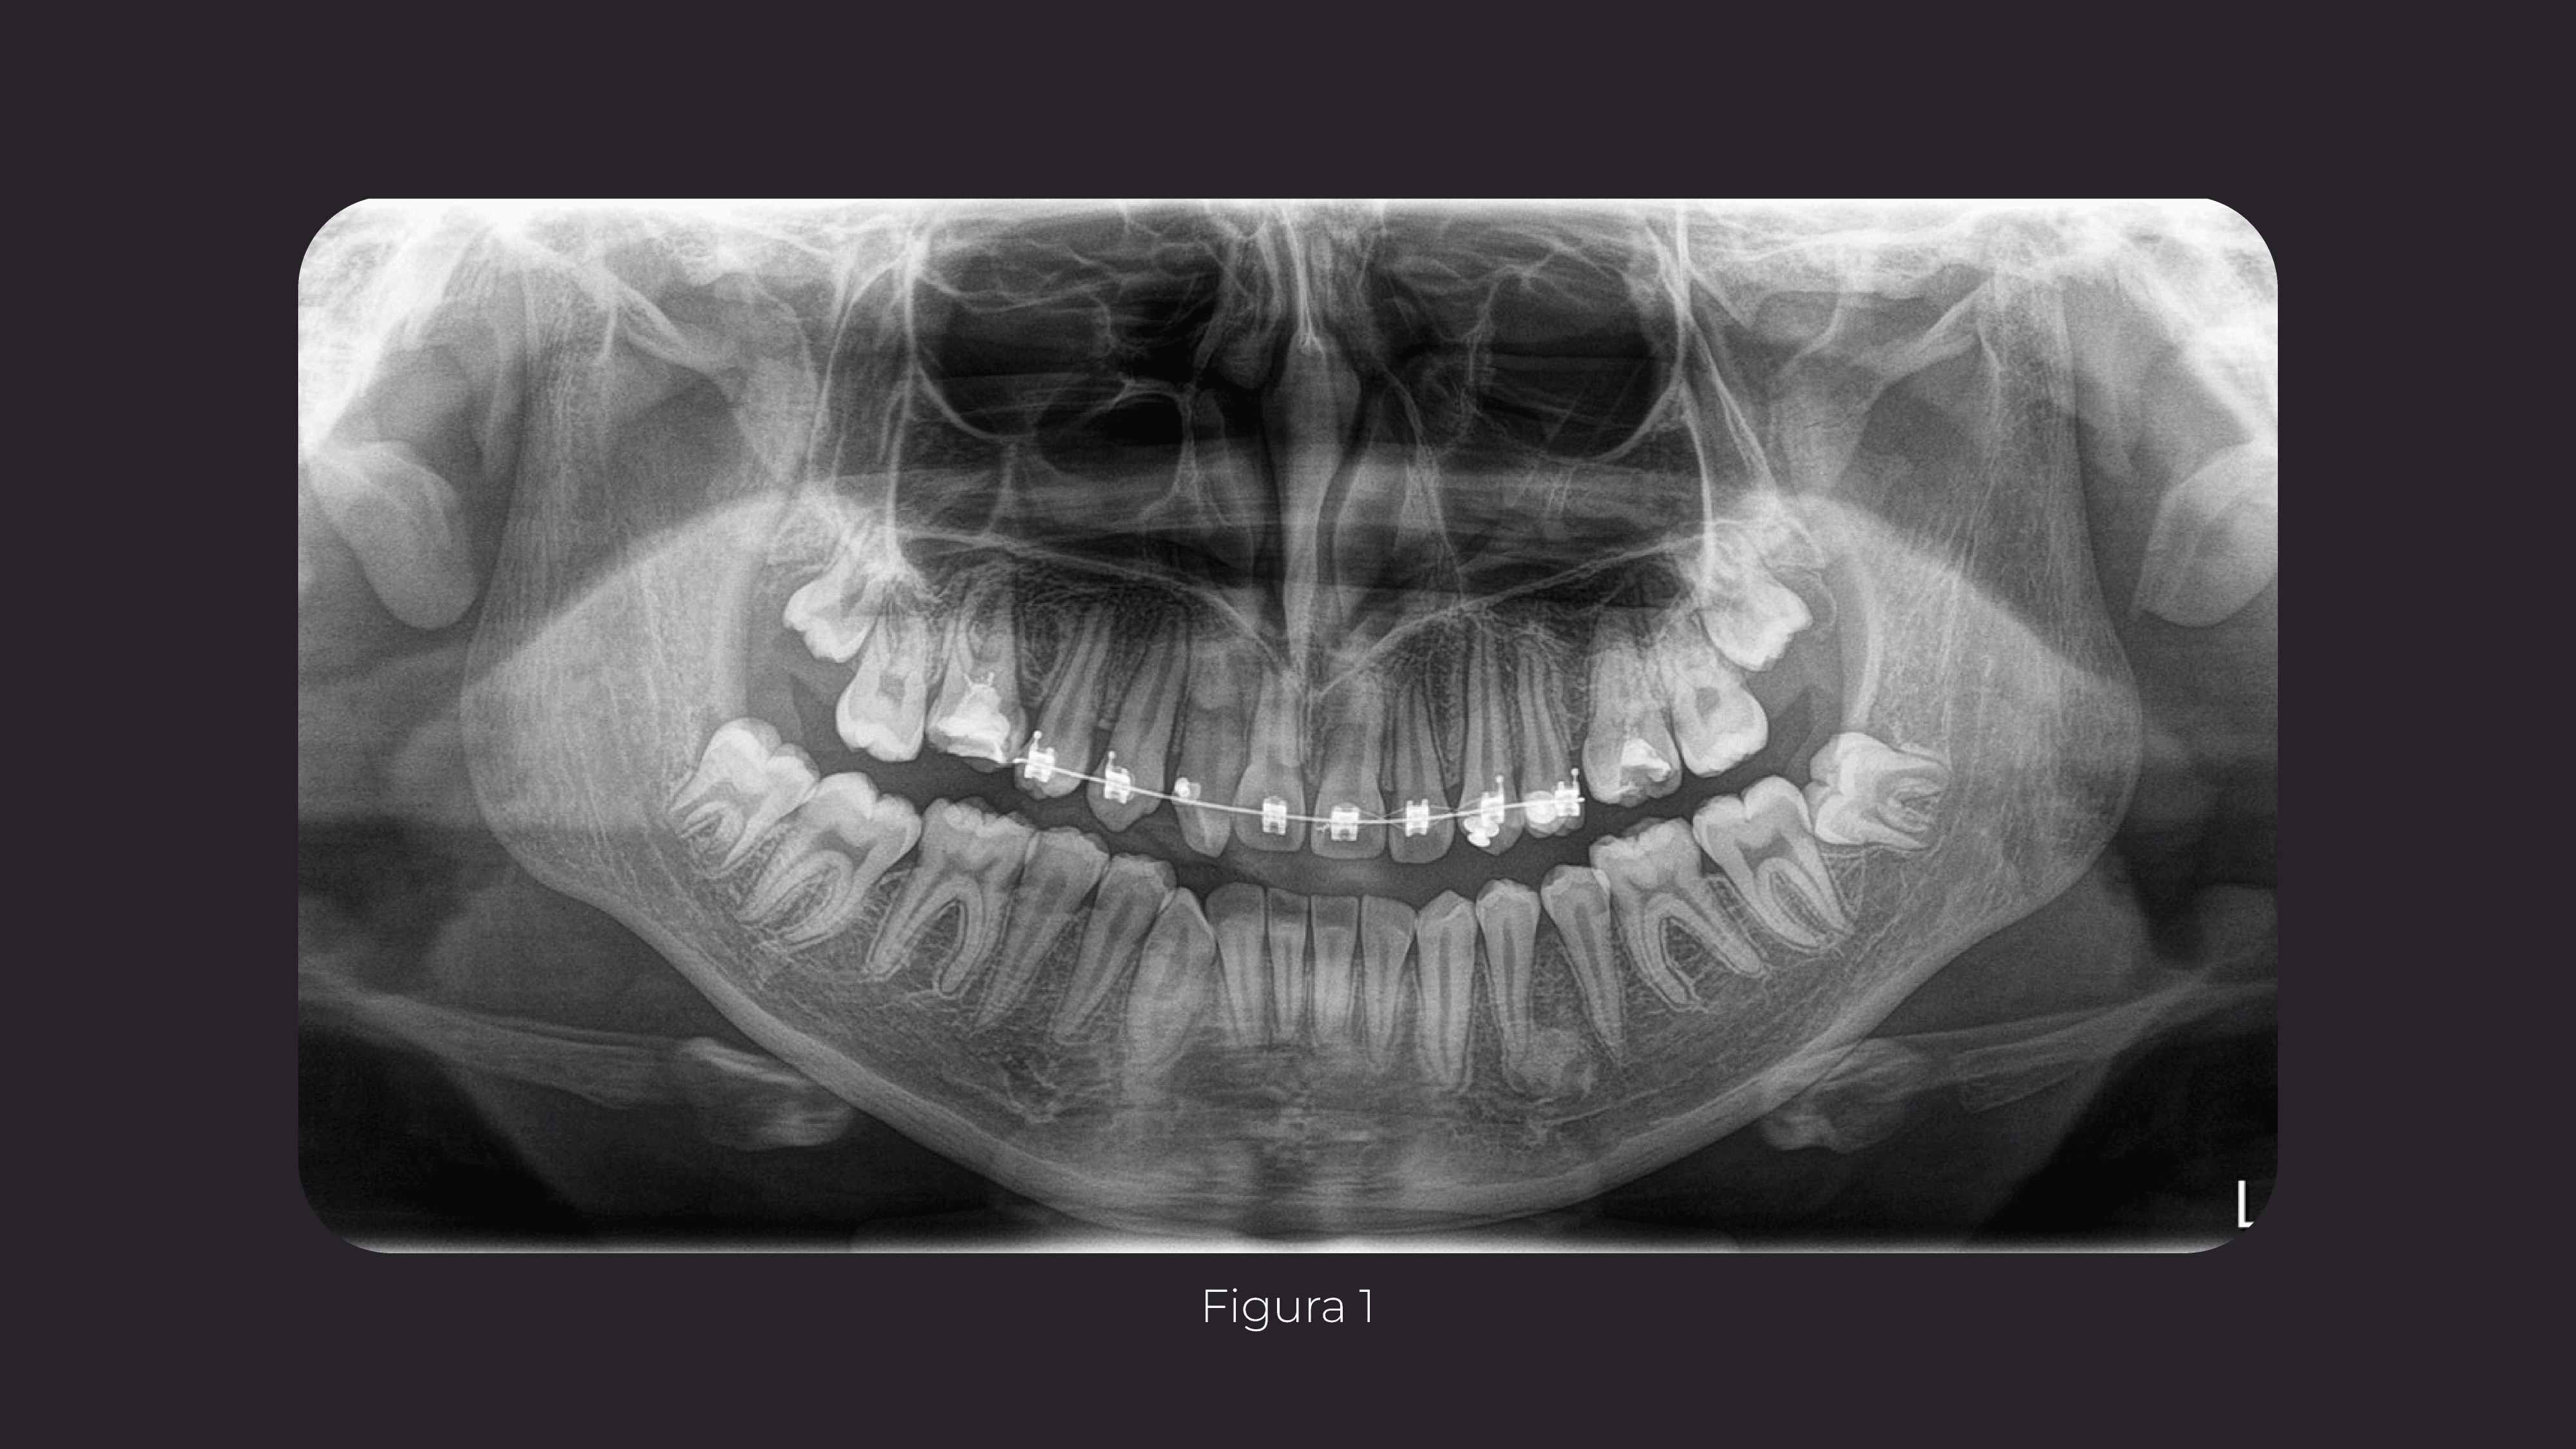

Paciente masculino, de 16 años de edad, sin antecedentes médicos contributorios, se presenta en consulta refiriendo aumento de volumen en cuerpo mandibular derecho con un año de evolución.

Figura 1

En la evaluación imagenológica se observa en la radiografía panorámica una imagen radiolúcida unilocular en relación a la pieza 48 que se encuentra en evolución intraósea en posición horizontal; la imagen está localizada en cuerpo y ángulo mandibular del lado derecho y presenta limites definidos con bordes corticalizados; se observa que la lesión se extiende hasta la región periapical de pieza 4.7 la cual presenta reabsorción radicular apical.

Signos radiográficos sugerentes de probable lesión quística.